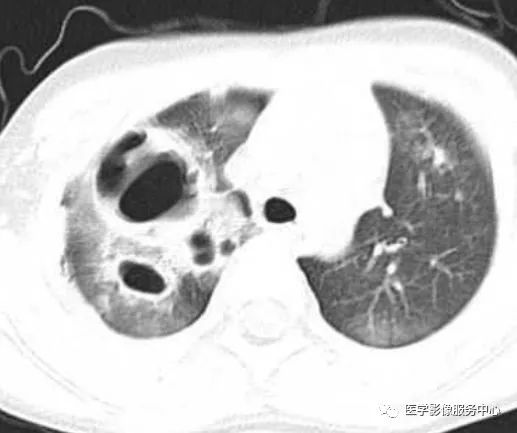

图13a

图13b

图13a,b.为LCH的多发囊肿。表现为不规则形态的奇异含气囊腔,厚壁/薄壁,上肺多,不累及膈角,患者有吸烟史。